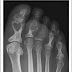

Cual es el diagnóstico? Sarcoidosis

Las lesiones líticas que se ven en las Rx son compatibles con granuloma sarcoide. Las manifestaciones de Sarcoidosis ósea ocurren temprano ...